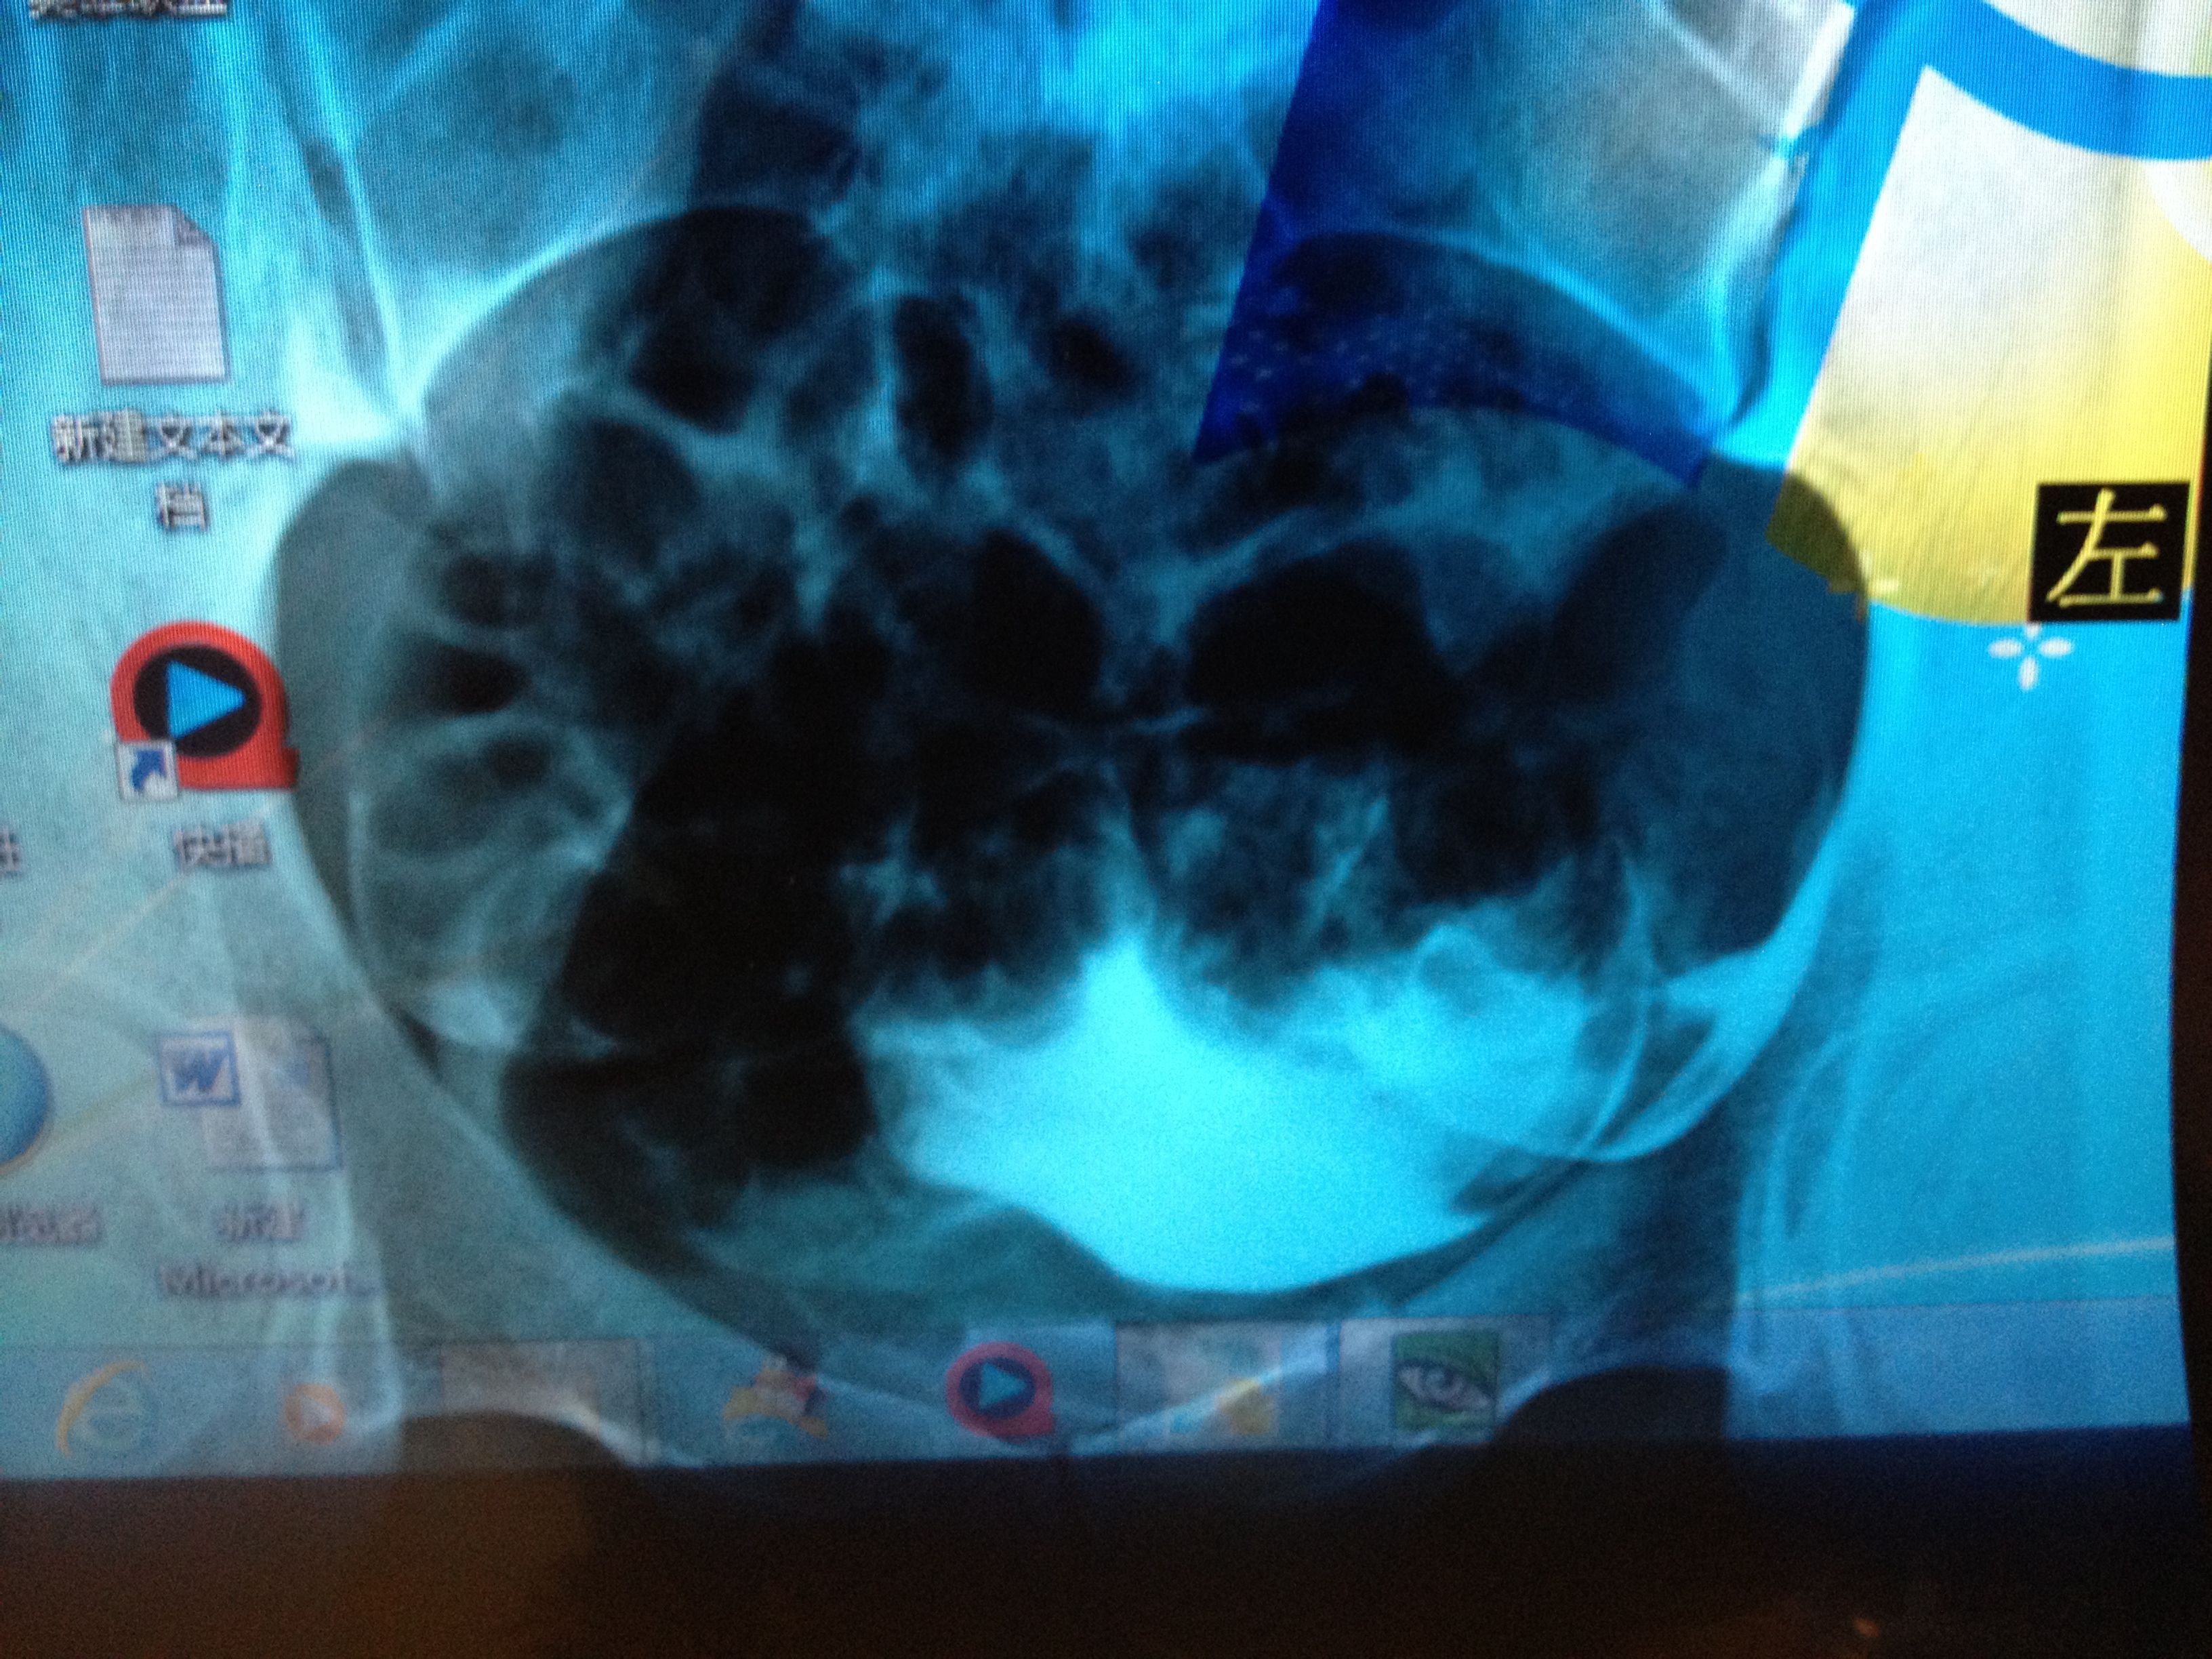

滑,并见部分照影剂自该侧伞端溢入盆腔,并见少许弥散。左侧输卵管大致 显影至壶腹区附近,进一步注入照影剂未见任何进展。第三张片于盆腔内可见散在片絮状及条弧状照影剂影,弥散尚可以。医生说右侧细,可能有炎症,左侧不通,两侧都得通水,我想问问有通水的必要吗?还有我的右侧是不是良好的?还是有炎症,还有偏细?应该怎么治疗?前两张是刚开始的,后两张是20分钟后的。还有现在拿到抗精子化验单有一项是阳性?怎么办?还有那个准吗?

病情分析: 您好,你的情况,考虑是输卵管堵塞积水的情况,一般药物效果是不好的,建议进行经腹腔镜导丝术,,估计费用大约需要3000元左右。注意术后抗炎处理,避免发生粘连。 指导意见: 在保守治疗效果不理想的情况下,建议在月经干净3-7天以后,去医院做腹腔镜微创手术治疗就可以,术后注意生殖系统的清洁卫生...,避免不洁性生活,加强锻炼,增强抗病能力,多以清淡食物为主,注意饮食规律。